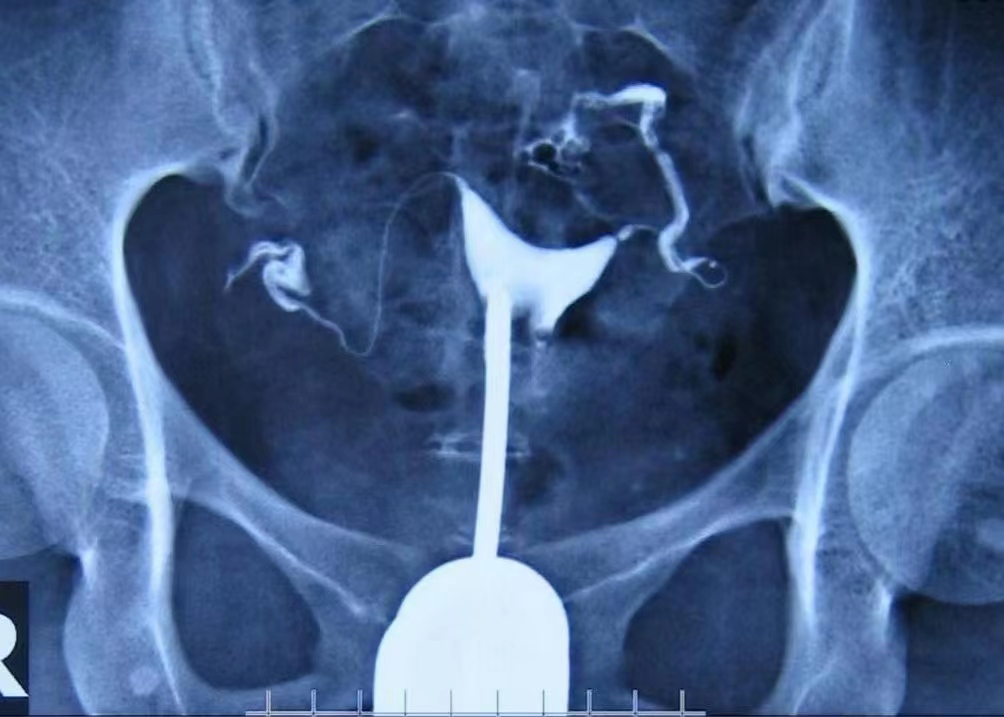

输卵管造影是一种用于检查输卵管通畅程度、形态和功能的医学影像技术。它是通过将一种特殊染料(造影剂)注入输卵管,然后在X光或超声波的照射下观察染料的流动情况,以评估输卵管是否正常。

造影剂通常在月经结束后3-7天内注入,并且在检查前需要避免性生活。整个过程需要摄片2次,一次是在造影剂注入后立即摄片,观察染料的流动情况和子宫腔的情况,另一次是在次日摄片,观察输卵管通畅程度和盆腔内的染料分布情况。

输卵管造影可以用于诊断多种妇科疾病,如不孕症、子宫异常出血、输卵管再通、肿瘤、畸形诊断和异物诊断等。对于不孕症患者,通过输卵管造影可以了解输卵管是否通畅,找出不孕的原因。对于有子宫异常出血的患者,通过造影可以了解出血原因和子宫粘膜及宫腔的情况。对于需要进行输卵管再通手术的患者,造影可以帮助医生了解输卵管情况,以决定是否可以进行手术。此外,造影还可以用于观察子宫肌瘤、附件肿瘤及其他盆腔脏器对子宫输卵管的影响,以及诊断子宫畸形和宫腔粘连等疾病。